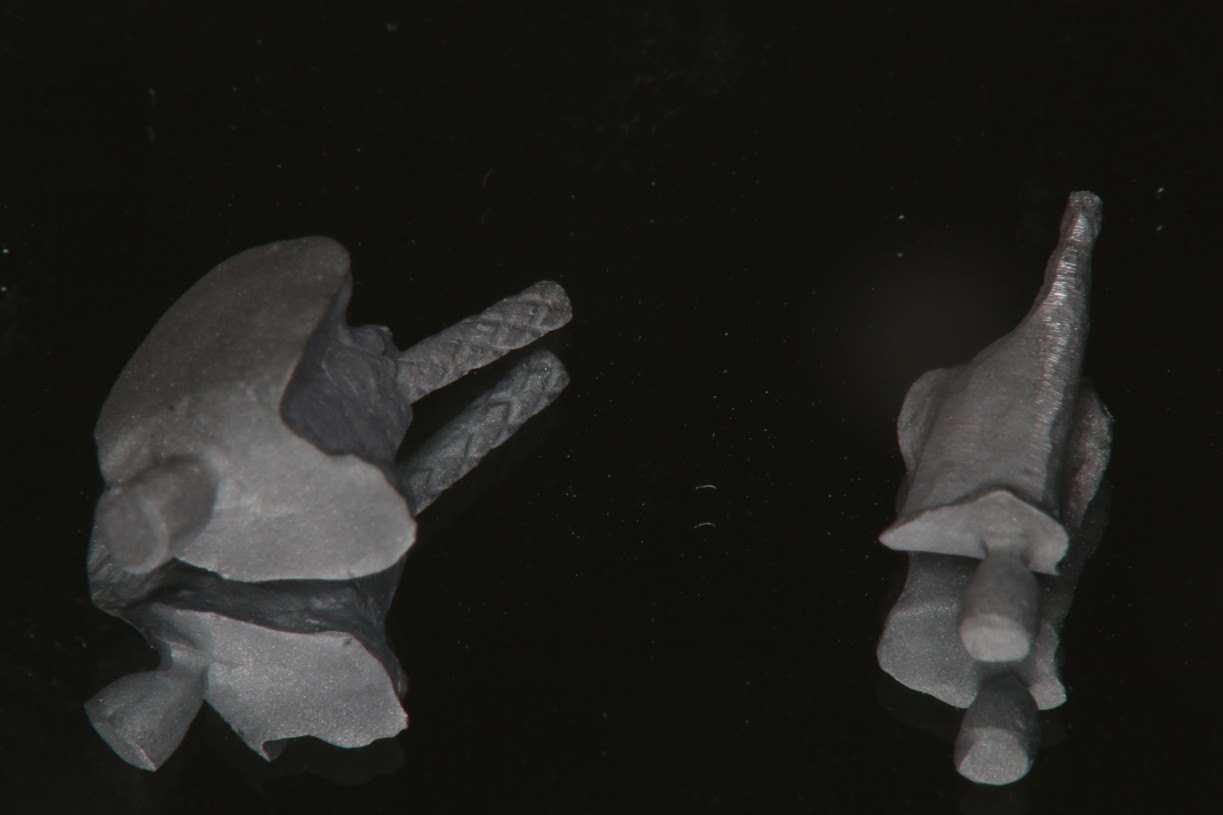

鑄造金屬釘柱